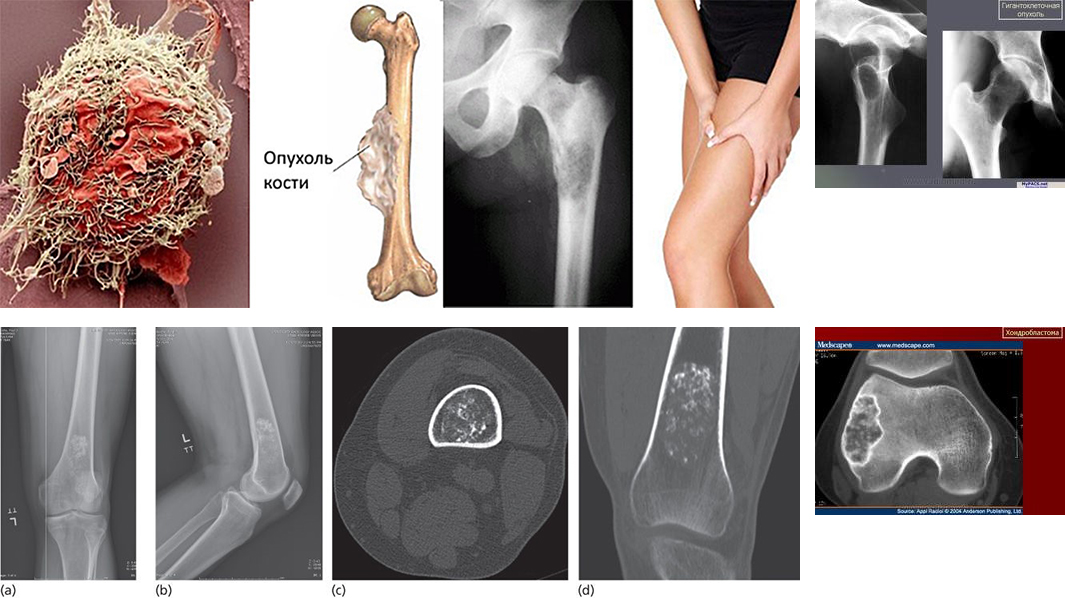

Отделение развернуто на 25 коек. Основное предназначение отделения - оказание высокотехнологичной медицинской помощи при последствиях и травмах, доброкачественных опухолях костной ткани, эндопротезирование (в том числе сложное и ревизионное), артроскопия крупных суставов военнослужащим, пенсионерам МО РФ, членам их семей и другим категориям граждан.

Основное направление научной работы - вопросы лечения раненых с огнестрельными ранениями костей конечностей с использованием современных методик; замещение дефектов костной ткани различными биоматериалами, после удаления доброкачественных и опухолеподобных новообразований; эндопротезирование тазобедренного, коленного, плечевого и локтевого суставов при травмах заболеваниях у пациентов разных возрастных групп.